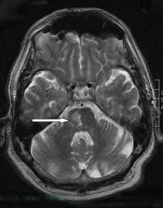

Lacunar infarcts are small infarcts in the deeper parts of the brain (basal ganglia, thalamus, white matter) and in the brainstem

• They are caused by occlusion of a single deep penetrating artery